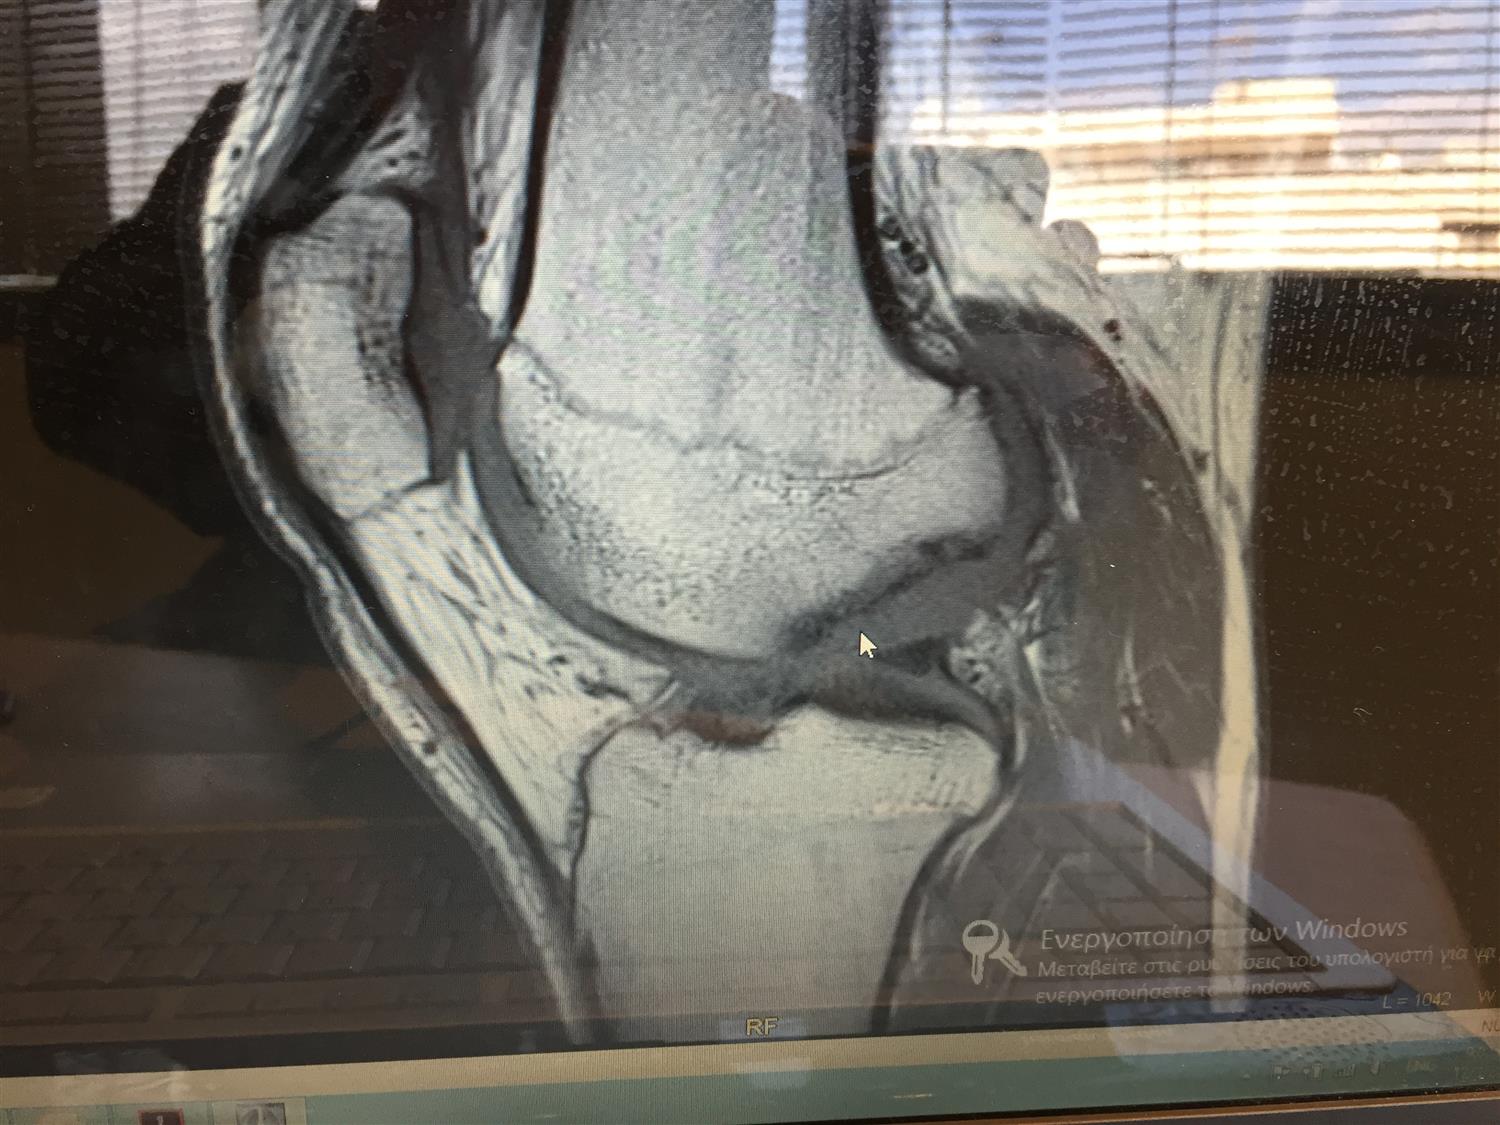

From www.researchgate.net

Unstable juvenile osteochondritis dissecans lesion that healed with Osteochondritis Dissecans Knee Brace osteochondritis dissecans (ocd) is a disorder resulting in focal breakdown of the subchondral bone, with. osteochondritis dissecans of the knee is a relatively rare condition,. the most common joints affected by osteochondritis dissecans are the knee, ankle and elbow, although it can also occur in other joints. symptoms of osteochondritis dissecans include pain, swelling, locking and. Osteochondritis Dissecans Knee Brace.